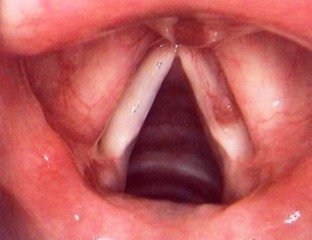

:电子喉镜下,声带小结、声带息肉手术

声带小结是一种较为常见的声带疾患,长期发作性声嘶,延治或者误治极容易导致声带息肉,保守治疗无效者,应该手术治疗。电子喉镜下,声带小结、声带息肉手术,是一种简单、方便的治疗方法,在内窥镜显示系统监视下,将声带的膜性组织进行切除,手术大约只需半个小时,就解除患者病痛。服务。